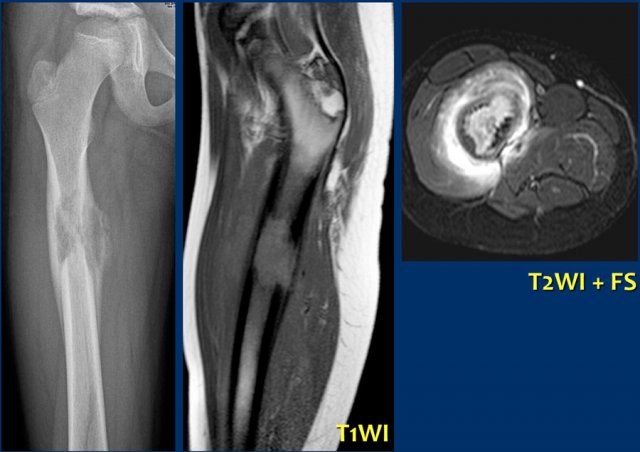

On the left a chondrosarcoma in the proximal tibia diaphysis.

The tumor is recognized by subtle calcifications in the proximal part.

The distal border is not well defined.

Notice endosteal scalloping at the medial side which is a hallmark of chondrosarcoma.

MR better defines the extension of the lesion.

MRI also demonstrates the endosteal scalloping.